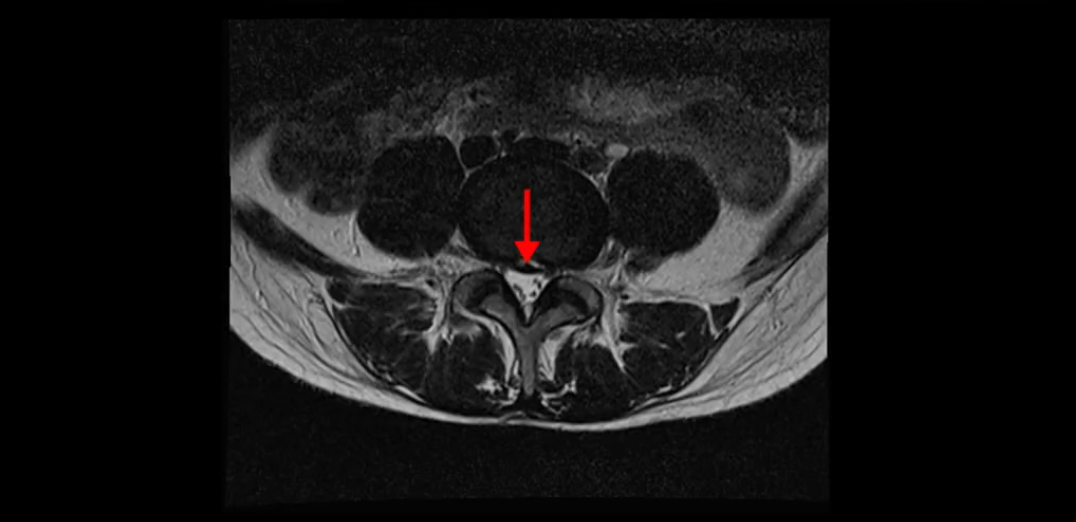

이분 MRI를 보시면 두 마디의 퇴행성디스크가 있습니다. 그리고 디스크가 조금씩 밀려 나와 있고요. 그런데 디스크 탈출 정도는 두 마디 다 심하지 않습니다. 4번 5번에는 디스크 탈출이 약간 있고,

5번 1번은 디스크 탈출이 가운데 쪽으로 살짝 있습니다.

중요한 것은 이 정도 경미한 탈출과 협착으로는 양쪽 다리가 저리고 아플 수가 없습니다.

이분 MRI를 보시면 퇴행성디스크가 있고 약간의 협착이 있지만 이 정도의 퇴행성디스크와 협착으로는 신경이 눌려서 양쪽 다리가 저리고 아픈 증상이 나올 수가 없습니다. 그래서 MRI와 이 환자분의 다리 증상이 매치가 안 된다고 하는 의사들이 많은 겁니다.